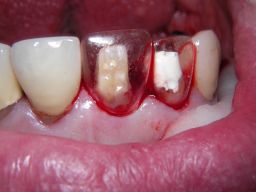

Am 28.2.06 erfolgte die endgültige Präparation (das "Beschleifen") aller 4 Zähne. Links das Modell, auf dem die Kronen gefertigt worden waren. Rechts kurz vorm Zementieren der Kronen am 13.3.06. Aus der Längendifferenz der Zähne rechts und links kann man darauf schließen, daß die Präparation tief unter dem Zahnfleisch erfolgen mußte. |